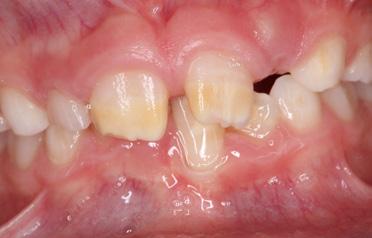

Glasionomerzemente sind ideal zur initi alen und provisorischen Versorgung von frisch eruptierenden MIH-Molaren, um weiterem Zahnhartsubstanzverlust vorzu beugen. Ihre einfache Handhabung auf grund nicht notwendiger Konditionie rungsschritte erleichtert die Anwendung besonders bei eingeschränkter Koopera tion der Patientin, des Patienten (Abb. 4, 5). Nachteilig ist die niedrige Biegefestig keit und minimale Abrasionsstabilität des Materials. Zum gegebenen Zeitpunkt sollten diese Provisorien jedoch durch definitive Restaurationen ausgetauscht werden [19].

Abb. 5: Glasionomerzementfüllung zum Schutz vor weiterem Substanzverlust und zur Therapie der Hypersensibilität.

Abb. 4:

Hypersensibler MIH Molar bei einem Patienten mit reduzierter Compliance. Als Erstversorgung wurde die Entscheidung für eine Glasionomer zementfüllung getroffen.

Les ciments verre ionomère sont idéaux pour la restauration initiale et provisoire de molaires MIH fraîchement éruptées, afin de prévenir une perte supplémen taire de substance dentaire dure. Leur manipulation simple en raison de l’ab sence d’étapes de conditionnement né cessaires facilite leur utilisation, notam ment lorsque la coopération du patient ou de la patiente est limitée (Fig. 4, 5). L’inconvénient provient de la faible résis tance à la flexion et de la stabilité mini male à l’abrasion du matériau. Le moment venu, ces restaurations provisoires doivent toutefois être remplacées par des restaurations définitives [19].

Fig. 4:

Molaire MIH hypersensible chez un patient présentant une compliance réduite. Le choix d’une obturation en ciment verre ionomère a été fait en première intention.

Fig. 5:

Obturation en ciment verre ionomère pour la protection contre une perte de substance supplémentaire et pour le traitement de l’hypersensibilité.